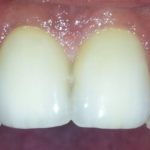

Traumatisme avec perte des 2 incisives centrales (2005)

Les deux incisives ne sont plus réimplantables

Deux implants et les couronnes céramiques, image radiologique

Deux couronnes sur implants. Notez l’architecture optimale festonnée de la gencive